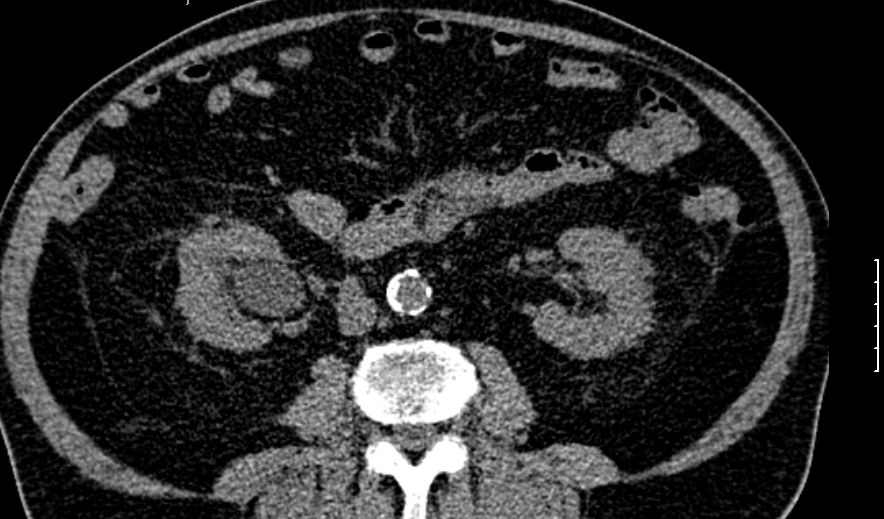

Der stark dilatierte Ureter links im kleonen Becken.

Ungewöhnlich Einmündung des dilatierten Ureters durch die Prostata in die Blase.